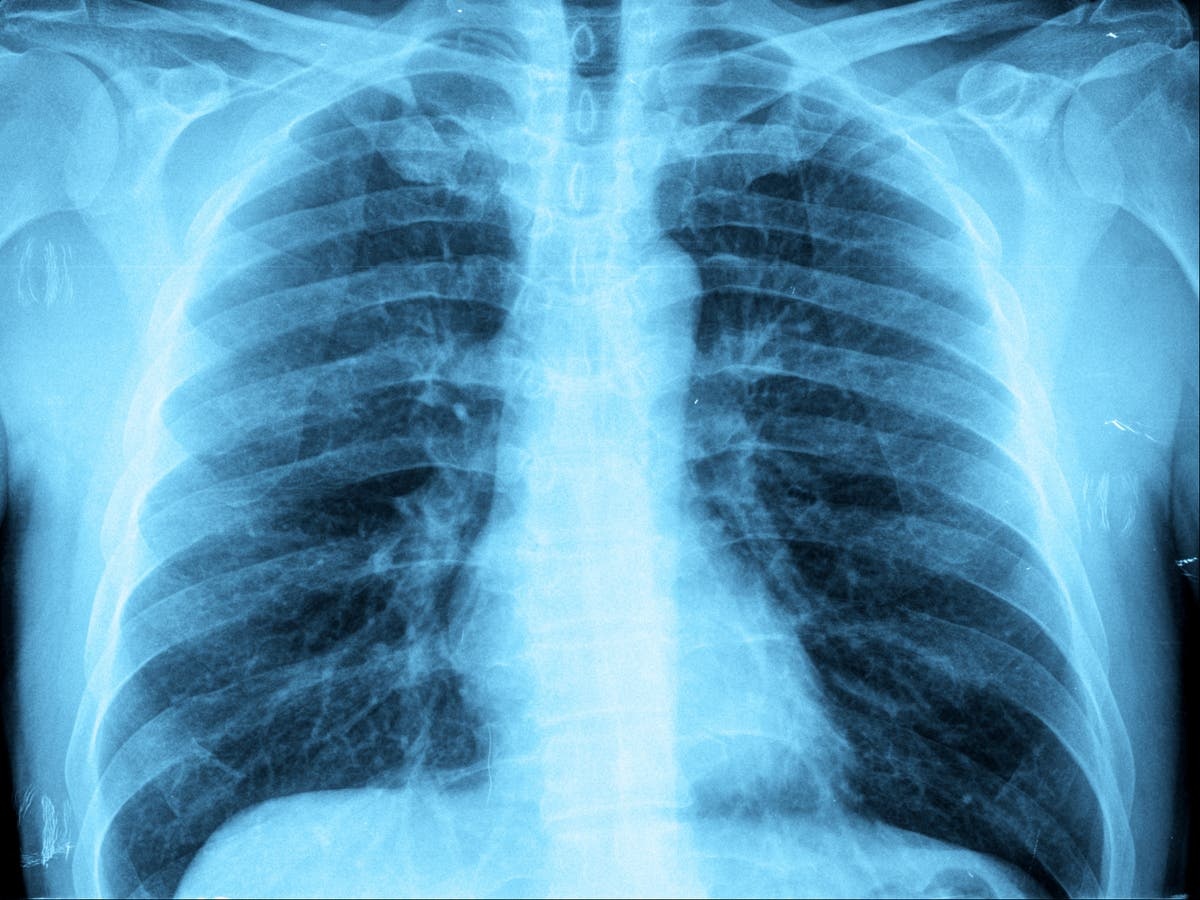

Media twierdzą, że choroba na pewno nie ma nic wspólnego z Chinami. Na razie pojawiła się w Ohio, stwierdzono 145 przypadków i nazwaną ją "epidemią".